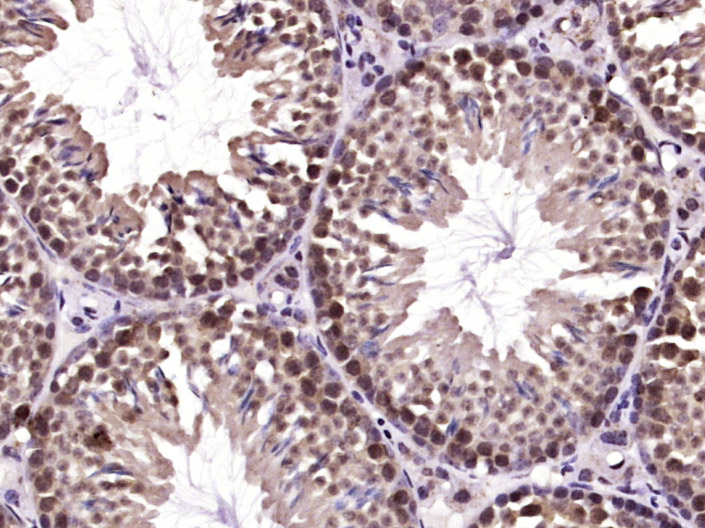

| 英文名称 | SHARPIN Rabbit pAb |

| 中文名称 | 线性泛素链相关蛋白SHARPIN抗体 |

| 产品应用 | IHC-P=1:100-500, IHC-F=1:100-500, IF=1:100-500 Not yet tested in other applications. |

| 交叉反应 | Mouse (Human, Rat, Dog) |

| 背景资料 | SHARPIN is a 387 amino acid protein that localizes to the cytoplasm and contains one RanBP2-type zinc finger. Expressed at high levels in placenta and skeletal muscle and present at lower levels in colon, brain, heart, liver, kidney, lung, thymus and small intestine, SHARPIN interacts with Shank 1 and is thought to play a role in the control of inflammatory responses and in the overall development of the immune system. SHARPIN exists as three alternatively spliced isoforms and shares 73% sequence identity with its mouse counterpart, suggesting a conserved role between species. The gene encoding SHARPIN maps to human chromosome 8, which consists of nearly 146 million base pairs, houses more than 800 genes and is associated with a variety of diseases and malignancies. |

| {IHC-P} | {1:100-500} |

| {IHC-F} | {1:100-500} |

| {IF} | {1:100-500} |